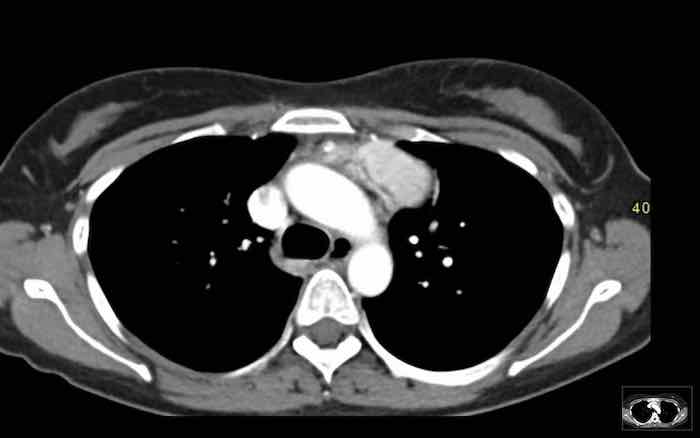

Các hình ảnh này của một bệnh nhân nam 60 tuổi có đau ngực, được chụp CT ngực để đánh giá điểm vôi hóa mạch vành.

Hãy phân tích hình ảnh trước.

Nhận định của bạn là gì?

Có một khối đặc ở trung thất và các tổn thương màng phổi.

Các tổn thương màng phổi chỉ xuất hiện ở bên phải, đây là đặc điểm điển hình của di căn màng phổi kiểu “nhỏ giọt” (pleural drop metastases) của thymoma.

Chúng là kết quả của sự xâm lấn trực tiếp vào màng phổi, không phải di căn theo đường máu, và chỉ xuất hiện ở một bên.

Hình PET cho thấy khối ở trung thất và nhiều tổn thương di căn màng phổi chỉ ở bên phải.